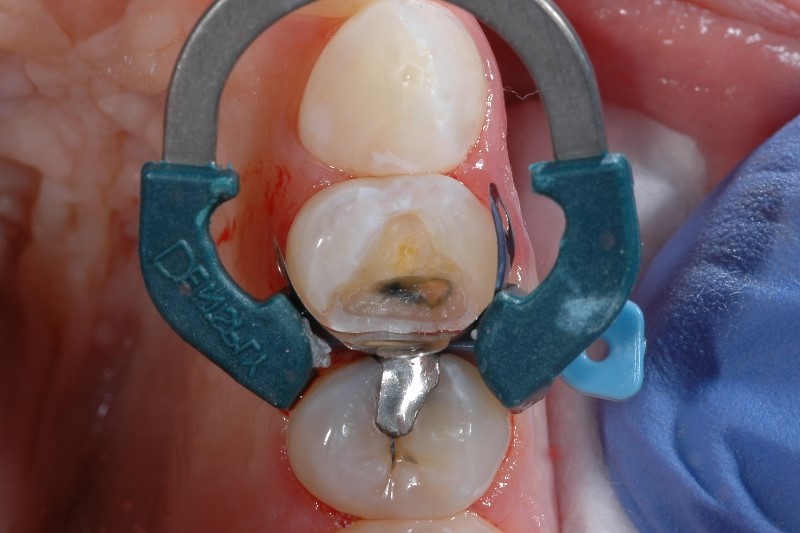

Sensitivity caused by inadequate tooth isolation

Proper tooth isolation is key in any phase of the Class II restoration, as it prevents saliva and blood from contaminating the restorative field. If the restorative field is contaminated, the physical properties and ultimate success of the restoration may be compromised, leading to post-op sensitivity and patient discomfort.

How to avoid sensitivity caused by inadequate tooth isolation

If you have trouble with isolation, you’re not alone - 97% of clinicians say that achieving proper isolation of a Class II cavity is difficult in at least 1 out of 10 cases.2 Besides common measures for isolation, consider the importance of a well-adapted matrix. Using matrix systems developed specifically for placing composite materials, like our Palodent® V3 Sectional Matrix System helps to achieve a tight seal at the gingival margin.